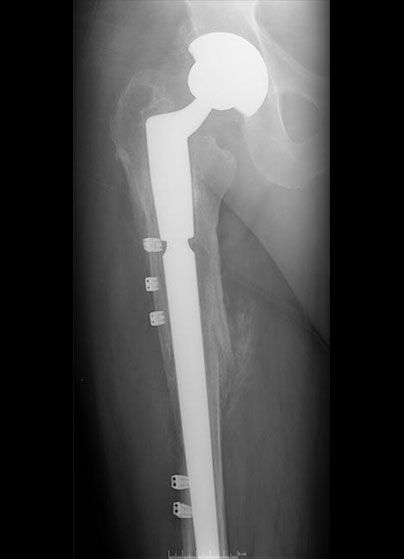

Failed THR

Revised THR